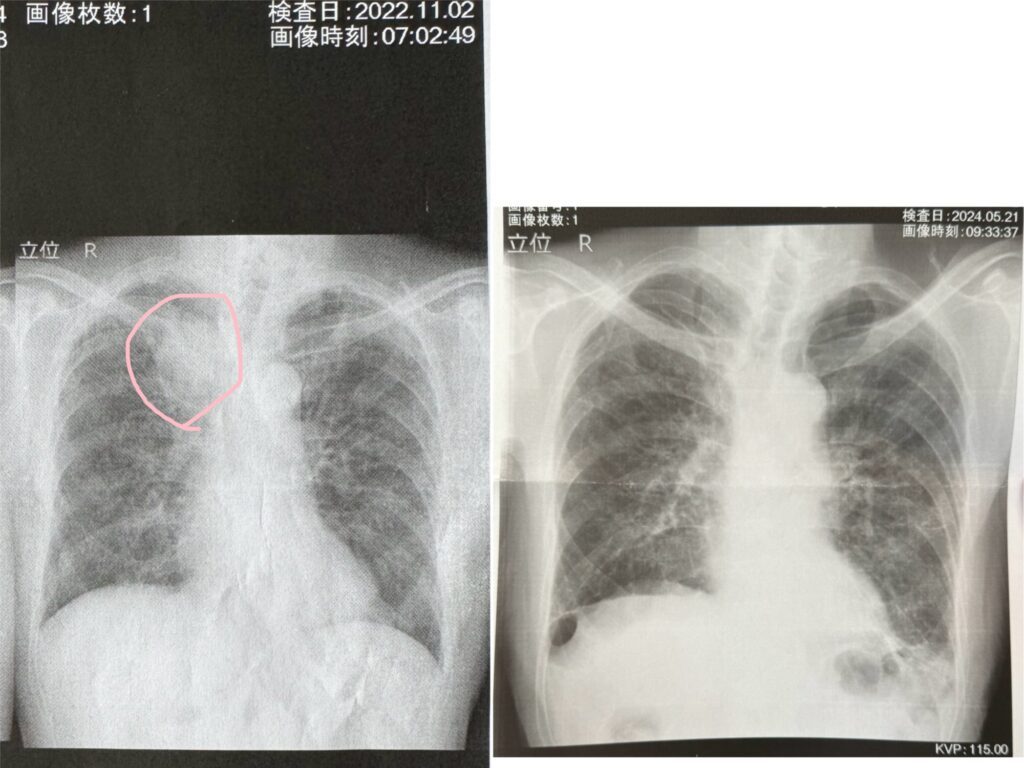

おじいちゃんの肺の様子(@asobiworldさんより提供)